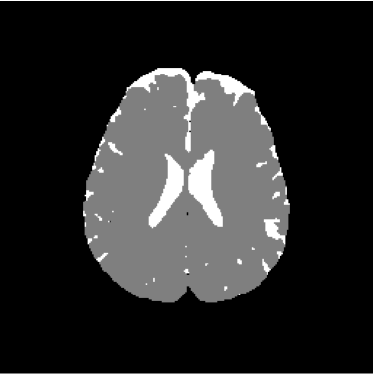

Figure 1: Axial DW-MR image of 13th slice with diffusion exponent of 0 s/mm2

To perform the training we chose 13th slice of each volume sample (figures 1, 2 and 3), once this slice shows the temporal corni of the lateral ventriculi. The exhibition of such structures facilitates the analysis of the specialist and helps him to find a correlation between data generated by our computational tool and a priori specialist knowledge. Furthermore, slice 13 presents a considerable amount of artifacts out of the cranial region.

Figure 13 shows the training set mounted on the 13th slice of the volume of ADC maps. Figures 14 and 15 show the ground truth volume and the 13th slice, respectively.

Figure 14: Ground truth image (13th slice) generated by polynomial net classification

Figure 28 shows 13th slice of classification result obtained by the use of the objective dialectical classifier. Figure 29 exhibits 13th slice of classification result after performing post-labeling, whilst figure 30 shows the entire volume generated by ODC classification.

The training process of ODC algorithm resulted in 6 classes. These classes were reduced to 4 after manual post-labeling, merging 3 classes out of brain region, namely image background, noise and cranial box. The post-labeling is manual because all 3 cited regions are statistically different and, consequently, they are merged due to our interest in classes more related to the brain regions. On figure 29 it is possible to notice that ODC was able to distinguish white matter from the gray matter present in the interface between liquor and white matter.

Figure 29: 13th slice of objective dialectical classification after post-labeling

Figures 33, 34 and 35 show binary images of 13th slice of ODC classification, showing liquor (cerebrospinal fluid, CSF), gray matter (GM) and white matter (WM), respectively, whilst figures 37 and 38 show the respective morphological spectra and accumulated morphological distributions. Both morphological spectra and accumulated morphological distributions were obtained using structure element square 3×3333\times 3 center (2,2)22(2,2).

Figure 34: 13th slice of gray matter volume detected by method ODC

Observing figure 34 indicating the detection of gray matter by the objective dialectical classifier, we can perceive the significative reduction of gray matter in brain frontal lobule, better seen in superior part of image. This lobule is directly related with the reduction of recent memory.